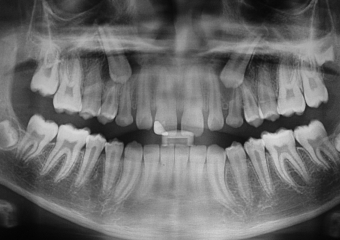

Rx Panorâmico - Caninos inclusos e intra-ósseos - Clínica Cliniface

Rx Panorâmico - Caninos inclusos e intra-ósseos